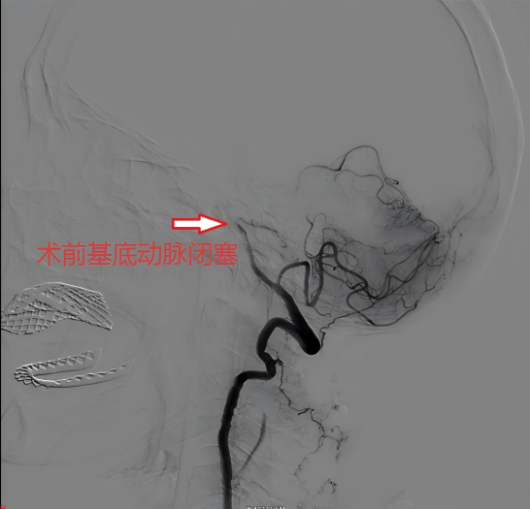

高龄+脑梗死这一情况,对神经内科医疗团队来说无疑是一个不小的挑战,保守治疗很有可能效果不佳导致严重后遗症,静脉溶栓又担心会出现出血导致更严重的后果,于是经过讨论分析,神经内科医疗团队为患者提出了神经介入的治疗方案,并在征求患者家属同意后,迅速为患者进行了“主动脉弓造影术+全脑血管造影术+基底动脉栓塞血栓抽吸术”,经过一个小时的努力,成功取出血栓,开通患者闭塞血管。此次手术取得良好治疗效果,术后第二天患者便可下床行走,一个星期后便顺利出院。